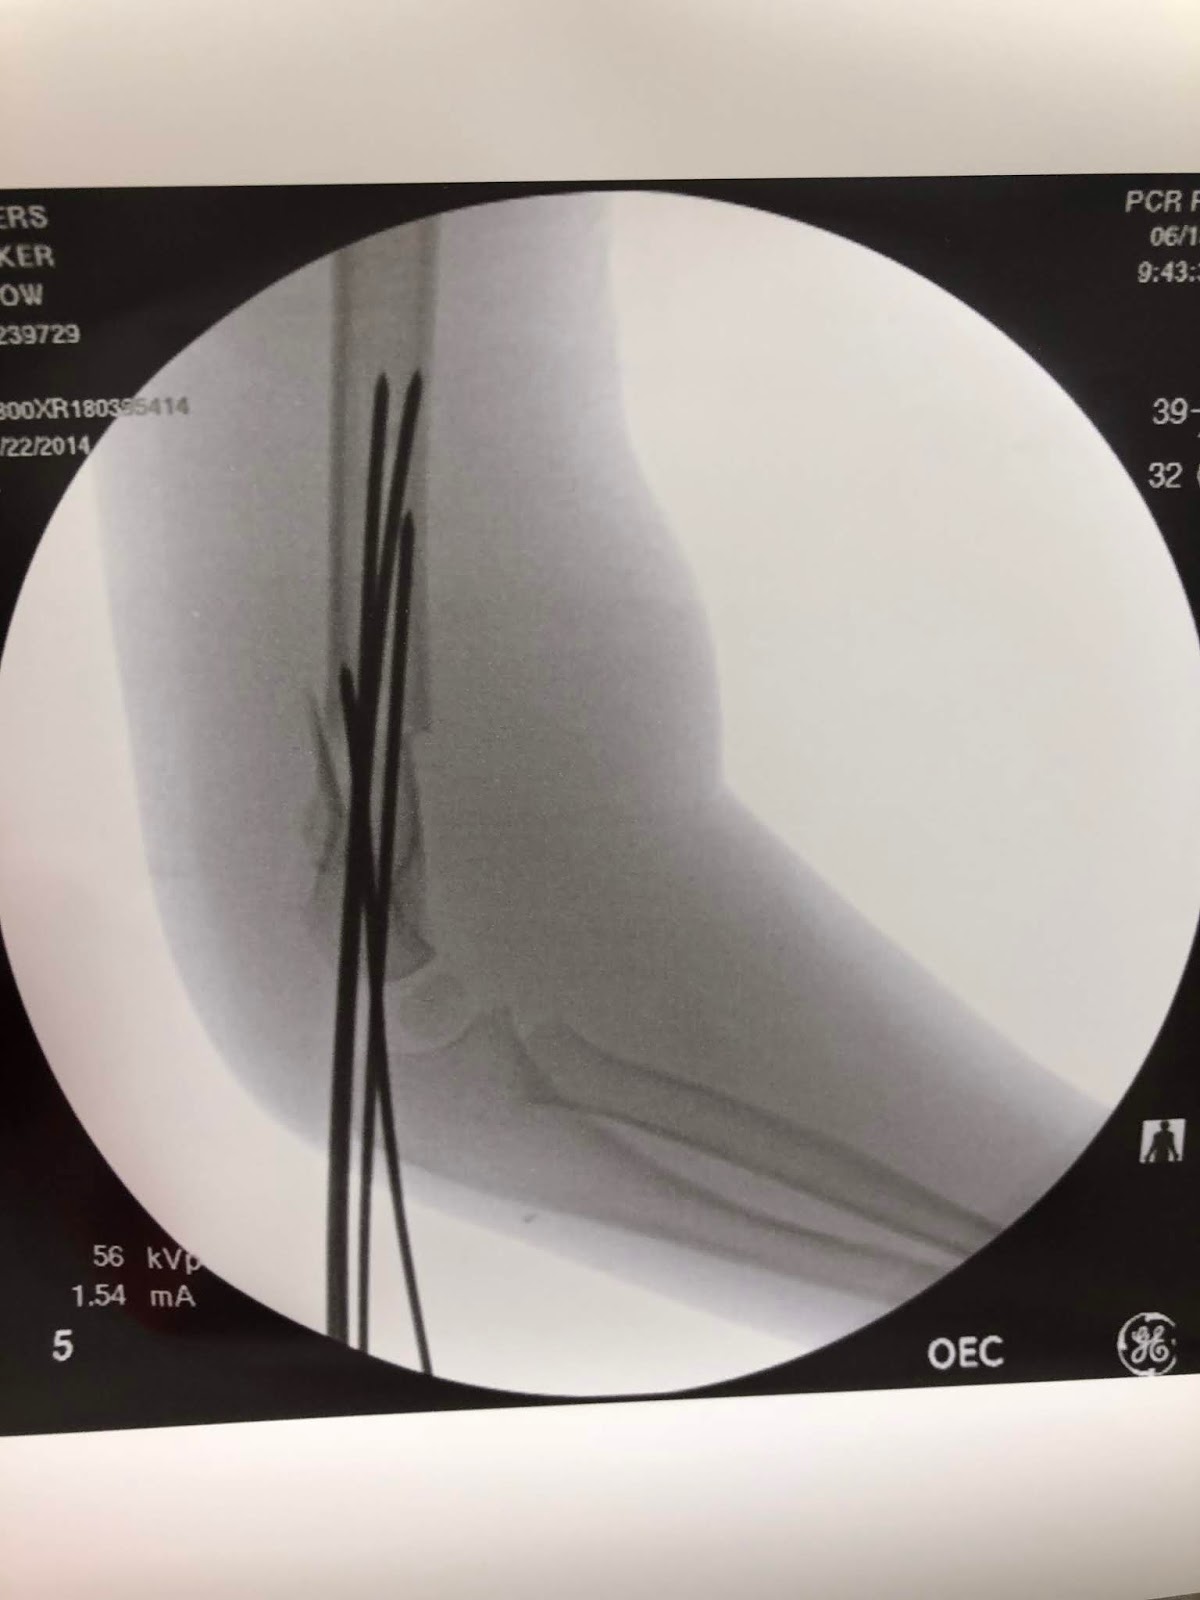

As you can see from the x-ray's it was in fact broken, and the pediatrician wouldn't touch it. He bandaged it back up and told us to go home, let him sleep and he would be in contact with a surgeon at Utah Valley Hospital and get back to us as soon as he could.

This is the picture that the surgeon took after he put Parker out. He told us that he is going to use it in lectures he gives in the future. Glad to be of assistance to you doc.

A job that normally needed 2 maybe 3 pins, took 4 pins to secure and the doctor was still nervous about it moving at all. These pins were so insane. They didn't have to cut him open at all, just basically stuck it through his skin. The reassured us it wouldn't hurt at all when they yanked them out in a few weeks.